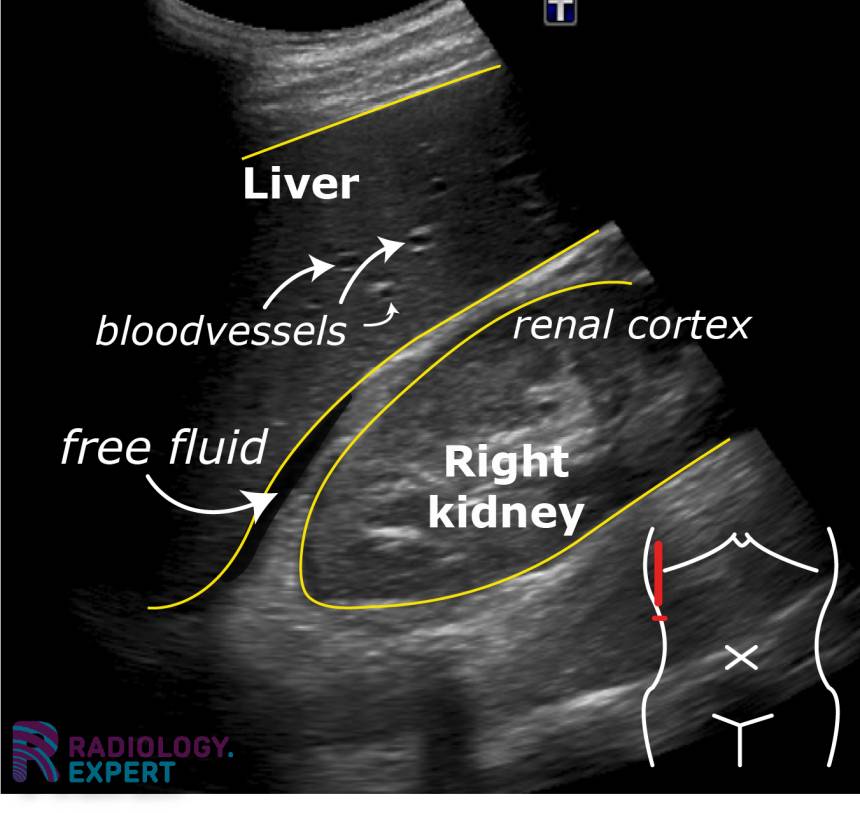

From www.radiology.expert

Abdominal ultrasound Turbid Free Fluid In Abdomen This condition often happens in. As the abdomen grows larger, the. Web the extra fluid leaks out of your veins and collects in your belly. Patients with a large volume of ascites can present with abdominal distension (which may be. If severe, it may be painful. Web lactate dehydrogenase (ldh), vascular endothelial growth factor (vegf), and other tumor markers can. Turbid Free Fluid In Abdomen.